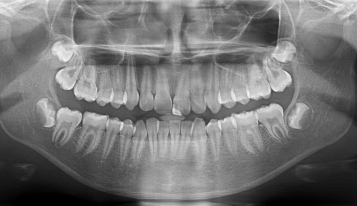

A radiografia dentária é dividida em dois tipos.

A radiografia intrabucal, que é realizada na parte interior da boca, e a extrabucal que é realizada na parte exterior da boca.

Radiografia intrabucal: o exame radiográfico realizado dentro da boca pode ser interproximal, periapical ou oclusal. O exame interproximal, também conhecido como bitewing, visa conhecer a mordida do paciente de forma detalhada. Dessa maneira, é possível identificar a presença de cáries, por exemplo. O exame periapical tem como foco o reconhecimento do dente por completo, incluindo a coroa dentária e seu osso de sustentação. Já o exame oclusal possibilita que o profissional observe o assoalho bucal. Assim, o profissional da odontologia consegue enxergar melhor a mordida a partir de cima.